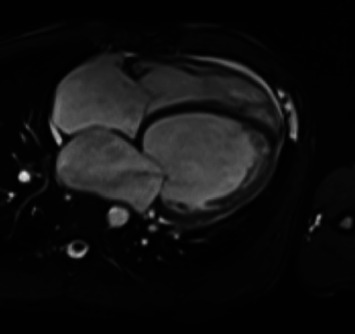

Background: Dilated cardiomyopathy is a leading cause of heart failure and heart transplantation. Among its etiologies, genetic variants account for up to 35% of cases. Variants in the FLNC gene have gained recognition due to their association with a higher risk of major ventricular arrhythmias and sudden cardiac death. Early identification and intervention are critical to improving patient outcomes. Case Presentation: We present the case of a 28-year-old male with no cardiovascular history who presented with ischemic stroke. Neurological improvement was noted following thrombolysis. Extensive testing ruled out infectious, thrombotic, and autoimmune causes. Subsequent evaluation revealed severe left ventricular systolic dysfunction (ejection fraction of 20%) and biventricular dilated cardiomyopathy. Genetic testing identified a likely pathogenic FLNC variant NM_001458.5(FLNC):c.1156G>T; p.Glu386∗, confirming the diagnosis of FLNC-associated dilated cardiomyopathy. Discussion: This case highlights the importance of investigating genetic causes in young patients presenting with unexplained dilated cardiomyopathy. Although truncating FLNC mutations are rare, they are associated with adverse outcomes, including major ventricular arrhythmias and sudden cardiac death. Atypical biventricular involvement suggests overlapping phenotypes, complicating the diagnostic process. Advanced imaging modalities, comprehensive management strategies, and early genetic testing are crucial to optimizing patient outcomes.